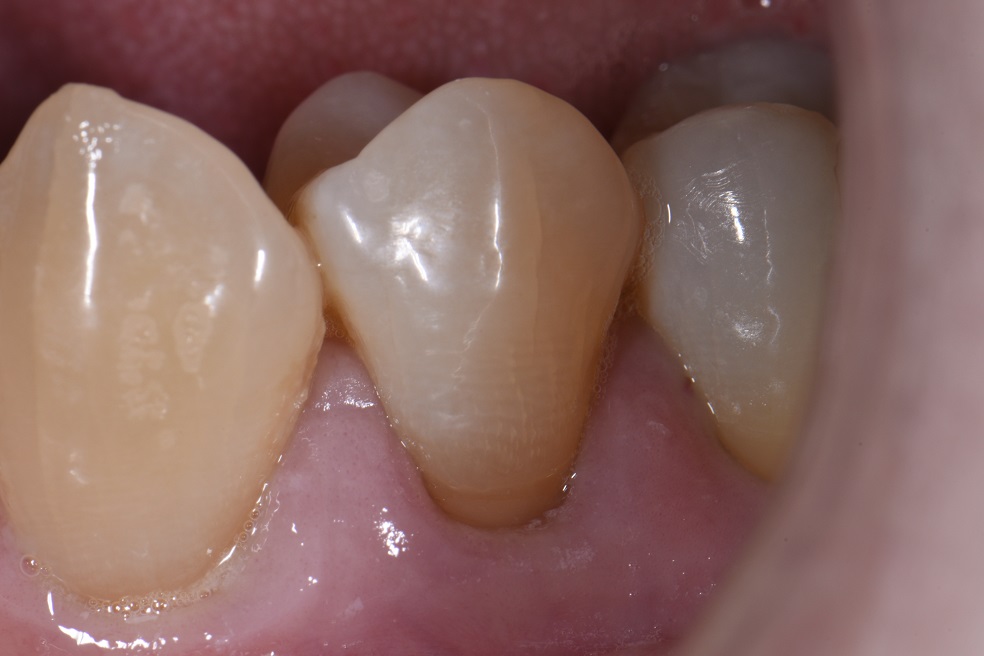

Cervical Abrasion Composite Resin Restorations What Is Abrasion In Dental  However, bigger problems arise when your bite is out of alignment, often causing more friction in places less prepared for it. If you’ve noticed the signs of. It can manifest as the loss of tooth structure, particularly. It can occur due to various factors, such as.   this condition, called dental abrasion, can occur when any foreign object causes friction. What Is Abrasion In Dental.

Cervical Abrasion Lesions Restored with GC Essentia U What Is Abrasion In Dental  If you’ve noticed the signs of. So, when two or more teeth come together, even with regular chewing with an ideal bite, some abrasion will occur.   this condition, called dental abrasion, can occur when any foreign object causes friction against your teeth and gradually wears away the enamel on the surface.   abrasion is the result of repeated contact. What Is Abrasion In Dental.